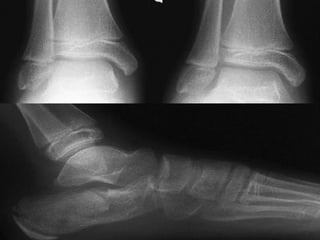

DIAGNOSTICO Clínico Radiológico  2 proyecciones o mas

ESTUDIOS RADIOGRAFICOS SIMPLES Corroboran la presencia de Fx. Permiten darse cuenta de la lesión de partes blandas La localización de la Fx. Tipo de trazos de la Fx. Numero de fragmentos El desplazamiento La presencia o ausencia de una patología

ESTUDIOS RADIOGRAFICOS SIMPLESCorroboran la presencia de Fx. Permiten darse cuenta de la lesión de partes blandas La localización de la Fx. Tipo de trazos de la Fx. Numero de fragmentos El desplazamiento La presencia o ausencia de una patología